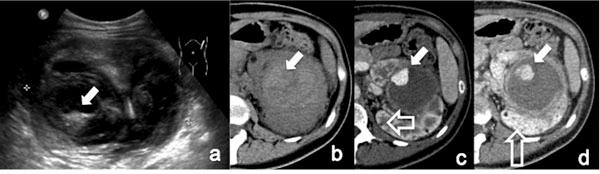

Acute vascular emergencies can arise from direct traumatic injury to the vessel or be spontaneous (non-traumatic).The vascular injuries can also be divided into two categories: arteial injury and venous injury.Most of them are life-treatening emergencies, sice they may cause an important ipovolemic shock or severe ischemia in their end organ and require prompt diagnosis and treatment.In the different clinical scenarios, the correct diagnostic approach to vascular injuries isn't firmly established and advantages of one imaging technique over the other are not obvious.Ultrasound (US) is an easy accessible, safe and non-invasive diagnostic modality but Computed Tomography (CT) with multiphasic imaging study is an accurate modality to evaluate the abdominal vascular injuries therefore can be considered the primary imaging modality in vascular emergencies.The aim of this review article is to illustrate the different imaging options for the diagnosis of abdominal vascular emergencies, including traumatic and non traumatic vessel injuries, focusing of US and CT modalities.

急性血管急症可由血管直接外伤引起,也可为自发性(非外伤性)。血管损伤也可分为两类:动脉损伤和静脉损伤。它们大多是危及生命的急症,因为它们可能导致重要的低血容量性休克或其终末器官的严重缺血,需要及时诊断和治疗。在不同的临床情况下,针对血管损伤的正确诊断方法尚未完全确立,一种成像技术相对于另一种成像技术的优势并不明显。超声(US)是一种易于获得、安全且无创的诊断方式,但多期成像研究的计算机断层扫描(CT)是评估腹部血管损伤的准确方式,因此可被视为血管急症的主要成像方式。本文综述的目的是阐述用于诊断腹部血管急症的不同成像选择,包括外伤性和非外伤性血管损伤,重点介绍超声和CT方式。